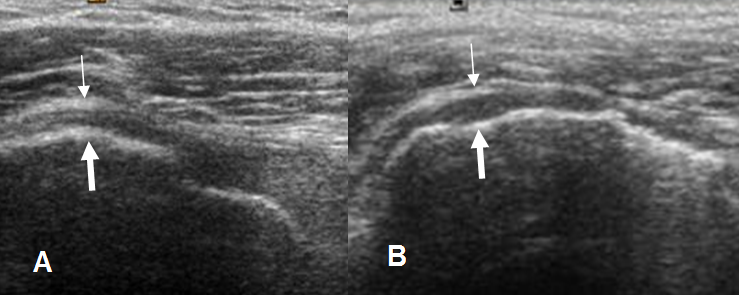

Fig 101. Ruptura parcial del supraespinoso.

Ecografía coronal. Area hipoecoica en el tendón, por ruptura parcial.

Fig 102. Ruptura parcial del supraespinoso.

A y B: Ecografía coronal. Zonas hipoecoicas en la superficie humeral, por ruptura parcial.